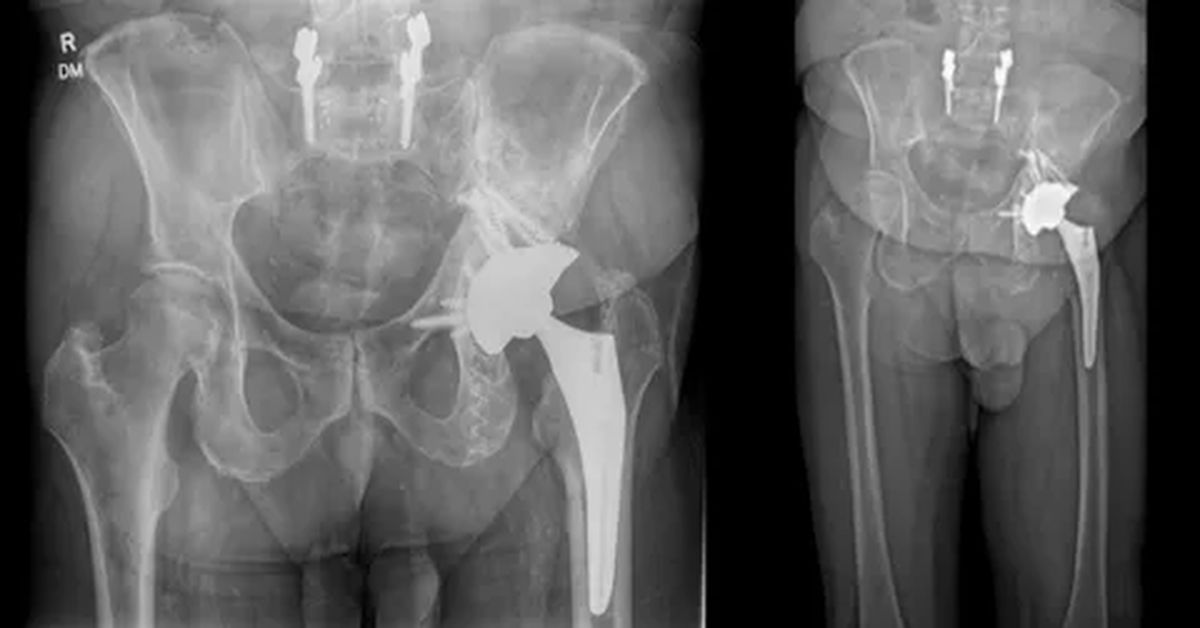

Eklem hastalıkları olan kişilerde uygulanan cerrahi yöntem, eklem yüzeylerini değiştirerek hareketi artırır ve ağrıyı azaltır. Total artroplasti, özellikle diz ve kalçada sık tercih edilir. Bu işlemde, hasarlı eklem parçaları özel protezlerle değiştirilir ve hastanın günlük yaşam kalitesi önemli ölçüde iyileşir.

Cerrahi sırasında eklem açılır ve hasarlı kıkırdak ile kemik dokusu dikkatlice çıkarılır. Gerekli ölçümler yapıldıktan sonra yapay eklem bileşenleri yerleştirilir. Bu bileşenler, genellikle metal karışımından üretilir. Uygulama sırasında kemik yüzeyine uygun bir şekilde yerleştirilir ve sabitlenir.